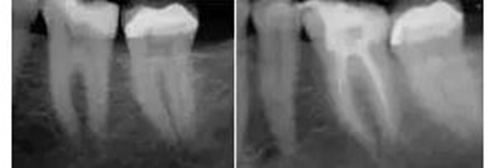

工作尖僅被置于開髓洞形的冠方。當(dāng)沖洗液占據(jù)整個(gè)根管系統(tǒng),開啟設(shè)備后震蕩波向所有方向傳導(dǎo),高效地清除有機(jī)組織殘留物。通過這種激光激活湍流現(xiàn)象,臨床醫(yī)師遵照PIPS使用方法,無需將工作尖放入每個(gè)根管,從而避免為了將標(biāo)準(zhǔn)針頭送入細(xì)小脆弱的根尖結(jié)構(gòu)(通常是根尖1/3)進(jìn)行沖洗而擴(kuò)大、去除更多的牙體組織。其結(jié)果是根管便利形態(tài)的獲得變得更保守、微創(chuàng)和仿生(圖3)。

圖3:左,術(shù)前。 右,經(jīng)PIPS處理后充填的術(shù)后片。牙齒預(yù)備至#25/06錐度。注意保守的便利形保持了更多的根管系統(tǒng)初始形態(tài)、減少了大號(hào)根管銼的使用、保存了更多的牙本質(zhì)結(jié)構(gòu)。